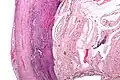

Pathology diagnosis of appendicitis can be made by detecting a neutrophilic infiltrate of the muscularis propria.

Micrograph of appendicitis and periappendicitis. H&E stain.

Micrograph of appendicitis showing neutrophils in the muscularis propria. H&E stain.